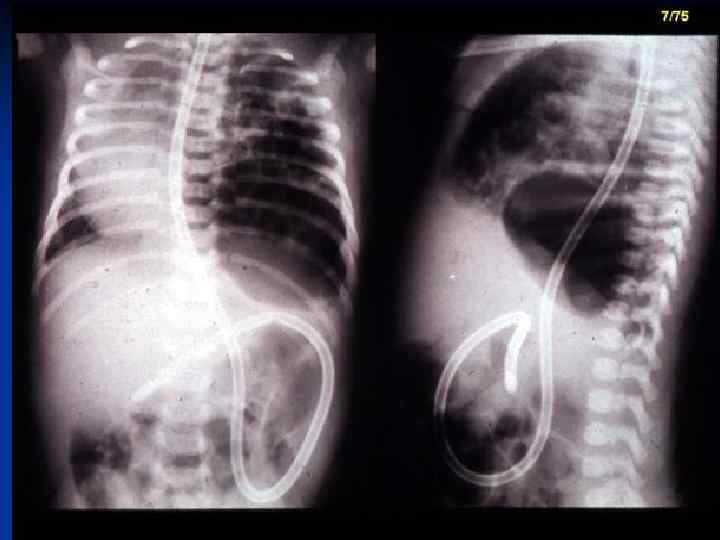

CDH